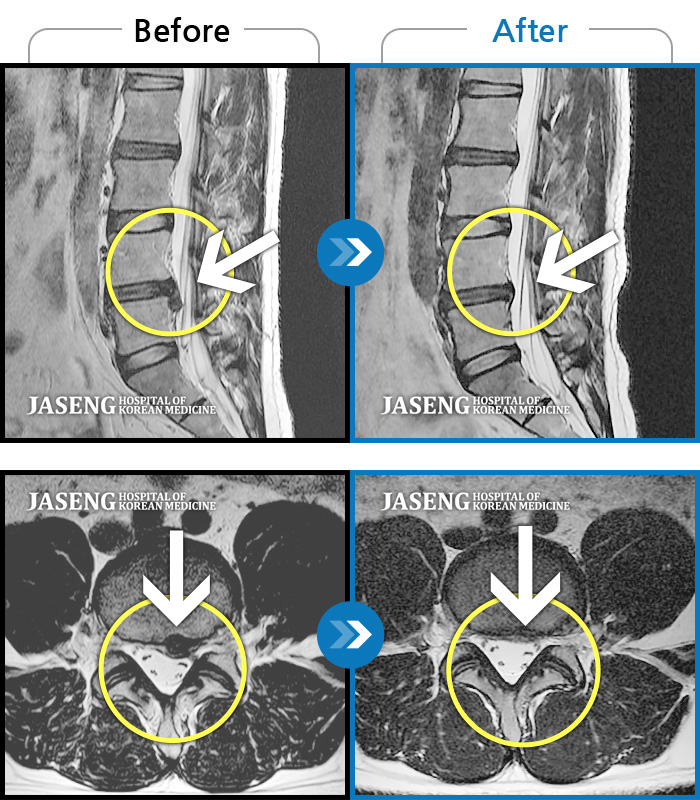

Before

After

환자에게 사전 동의를 받아 동일 조건에서 촬영되었습니다.

개인에 따라 치료 후 부작용이 발생할 수 있으니 의료진과 상담 후 치료를 진행하시기 바랍니다.

허리 통증, 우측 하지 후면부터 발가락 전체에 저림 증상

허리통증과 좌측 하지방사통